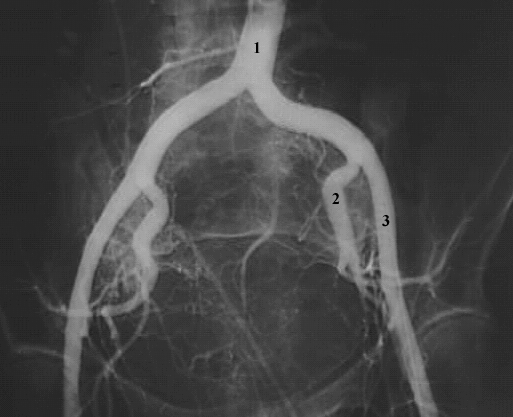

Pelvis & Perineum: Pelvic Arteriogram:

1. Abdominal Aorta

2. Internal iliac artery

3. External iliac artery